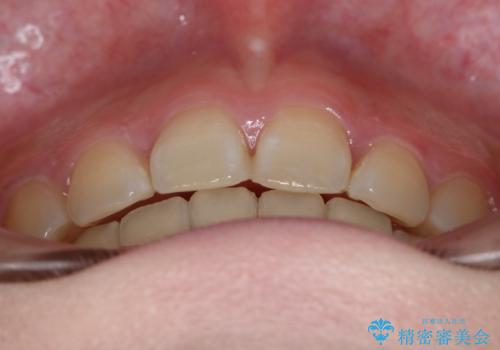

- 前歯のガタつきと口元の改善を主訴に来院されました。

なるべく目立たない装置が良いというご要望と、口元を引っ込めたいというご要望を両方達成するために今回はハーフリンガル装置を選択し治療計画の立案を行いました。

結果的に表の装置よりは期間が掛かりましたが、口元もしっかり下がり韓国美人な横顔になったと患者様にも喜んでいただけました。